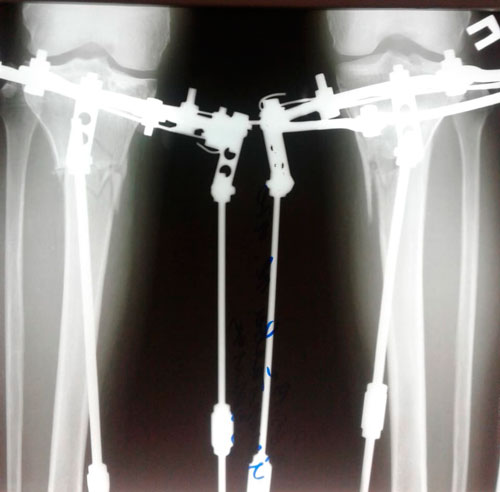

Исходник - 49 лет. Киргизия.

Дата операции - 12.04.2019г.

Вложения

IMG_2514-17-04-19-11-20.JPG

IMG_2510-17-04-19-11-20.JPG